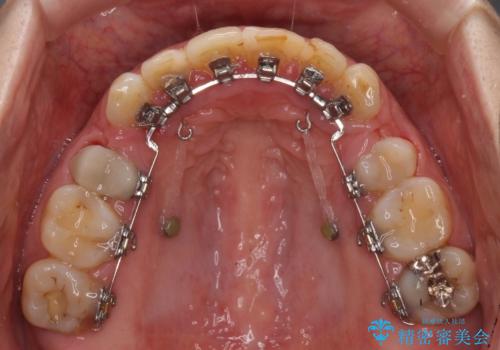

- ハーフリンガル

口元の突出感はあまり気になっていませんでしたが、上下の前歯の前後差が大きかったため、上顎左右の第一小臼歯を抜歯し、上顎が裏側装置であるハーフリンガルにて矯正治療を行うこととしました。

咬合力が非常に強く、スペースがなかなか閉じなかったことと、上下の正中が著しくずれてきてしまったため、下顎左側小臼歯を途中抜歯することとなりました。

歯の動きが鈍く、矯正治療だけで4年以上の期間を要することとなりました。